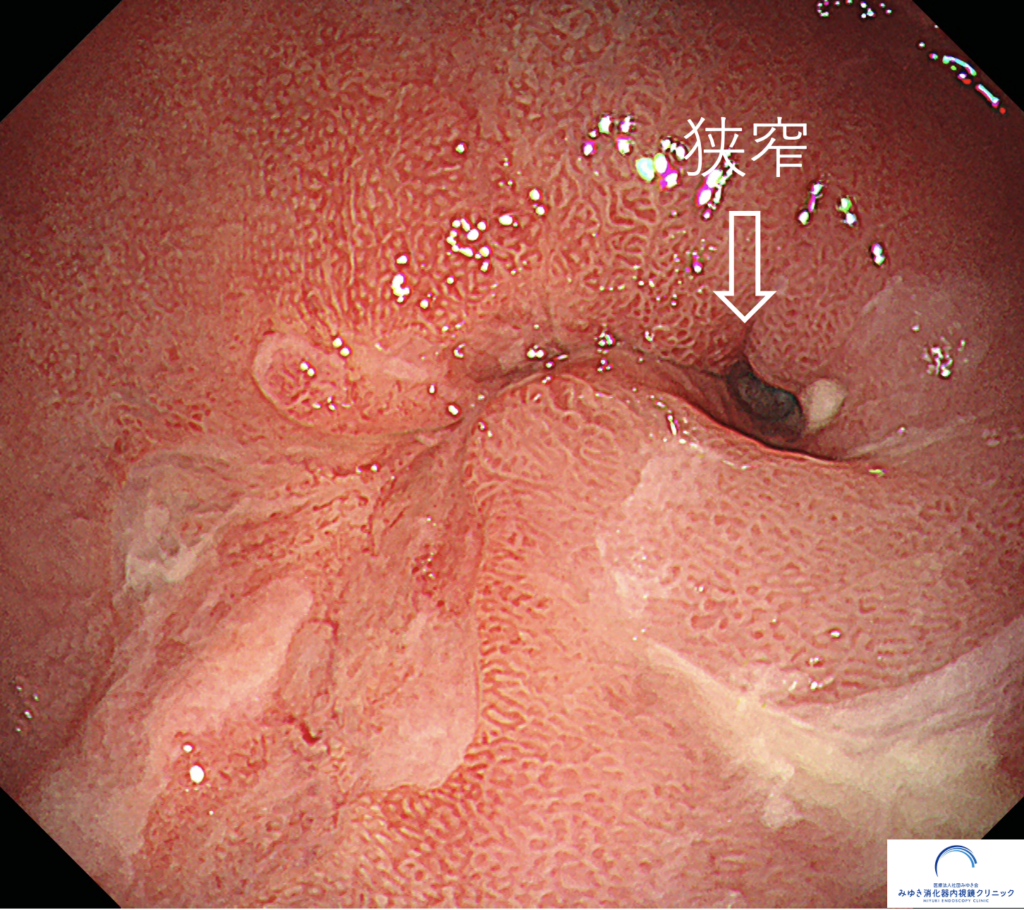

食事が胸につかえるため、胃カメラを行ったところ、食道が細くなっていました(狭窄)。狭窄部手前からの生検でバレット食道がんと診断されたため、ロボット手術をしていただきました。